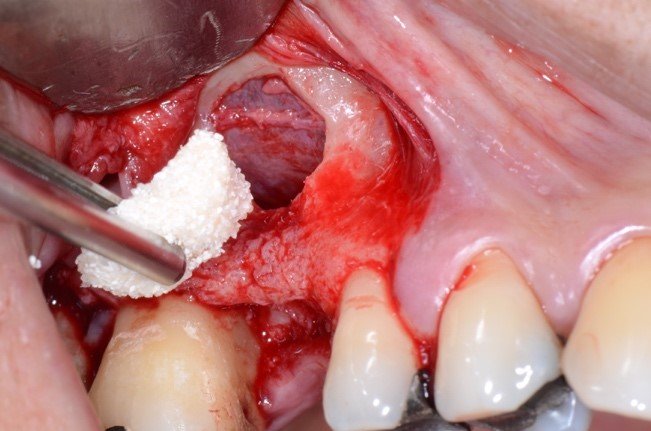

As figuras 16 e 17 mostram o transoperatório de um caso de hemorragia após dano a AAPS durante procedimento de osteotomia para rotação superior da janela óssea. A hemorragia durante a cirurgia trouxe dificuldades na visualização da membrana e a mobilização da janela para o interior da cavidade para formar o teto sobre a membrana sinusal. Somente após o preenchimento total com enxerto ósseo bovino particulado e cobertura com membrana hemostática de colágeno, houve diminuição do fluxo sanguíneo local. Mesmo com a manobra transoperatória, ocorreu a formação de extenso blefarohematoma periorbital e hematoma cérvico-facial. Segundo relato da paciente, o edema palpebral e na região parotídeo-masseterina provocaram dificuldade na abertura palpebral e bucal. As figuras 18 e 19 demonstram os hematomas já em regressão no 110 dia de pós-operatório (PO), já em uso de compressas mornas desde o 70 dia de PO, associado a moderada massagem local para drenagem hemo-linfática nos tecidos com pomada fibrinolítica.